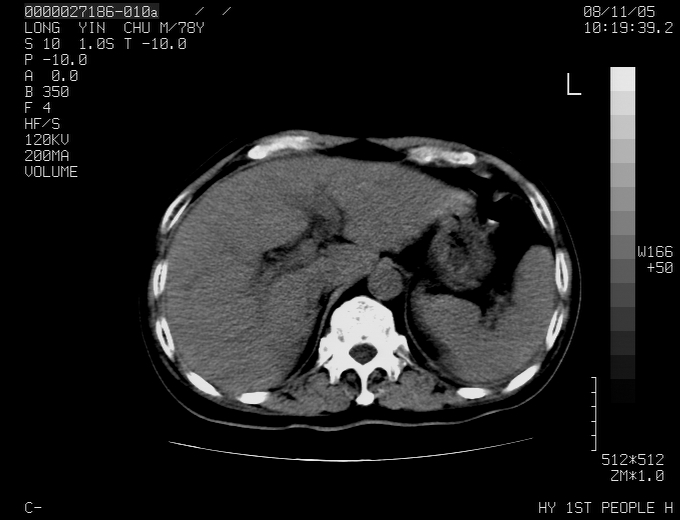

标题: CT16532:M78Y,肝脏病变,请会诊 [打印本页]

标题: CT16532:M78Y,肝脏病变,请会诊

腹胀,腹痛就诊,男性,78岁,外院b超未见异常。

肝ca,脾肾转移

考虑弥漫性肝癌并脾及双肾转移.双侧胸水.

图片质量欠佳:多考虑:左侧肾癌。脾脏转移!胸膜转移!

肝脾肾转移瘤可能性大,左肾不除外梗塞,双侧胸水

考虑弥漫性肝癌并脾及双肾转移,双侧胸水。